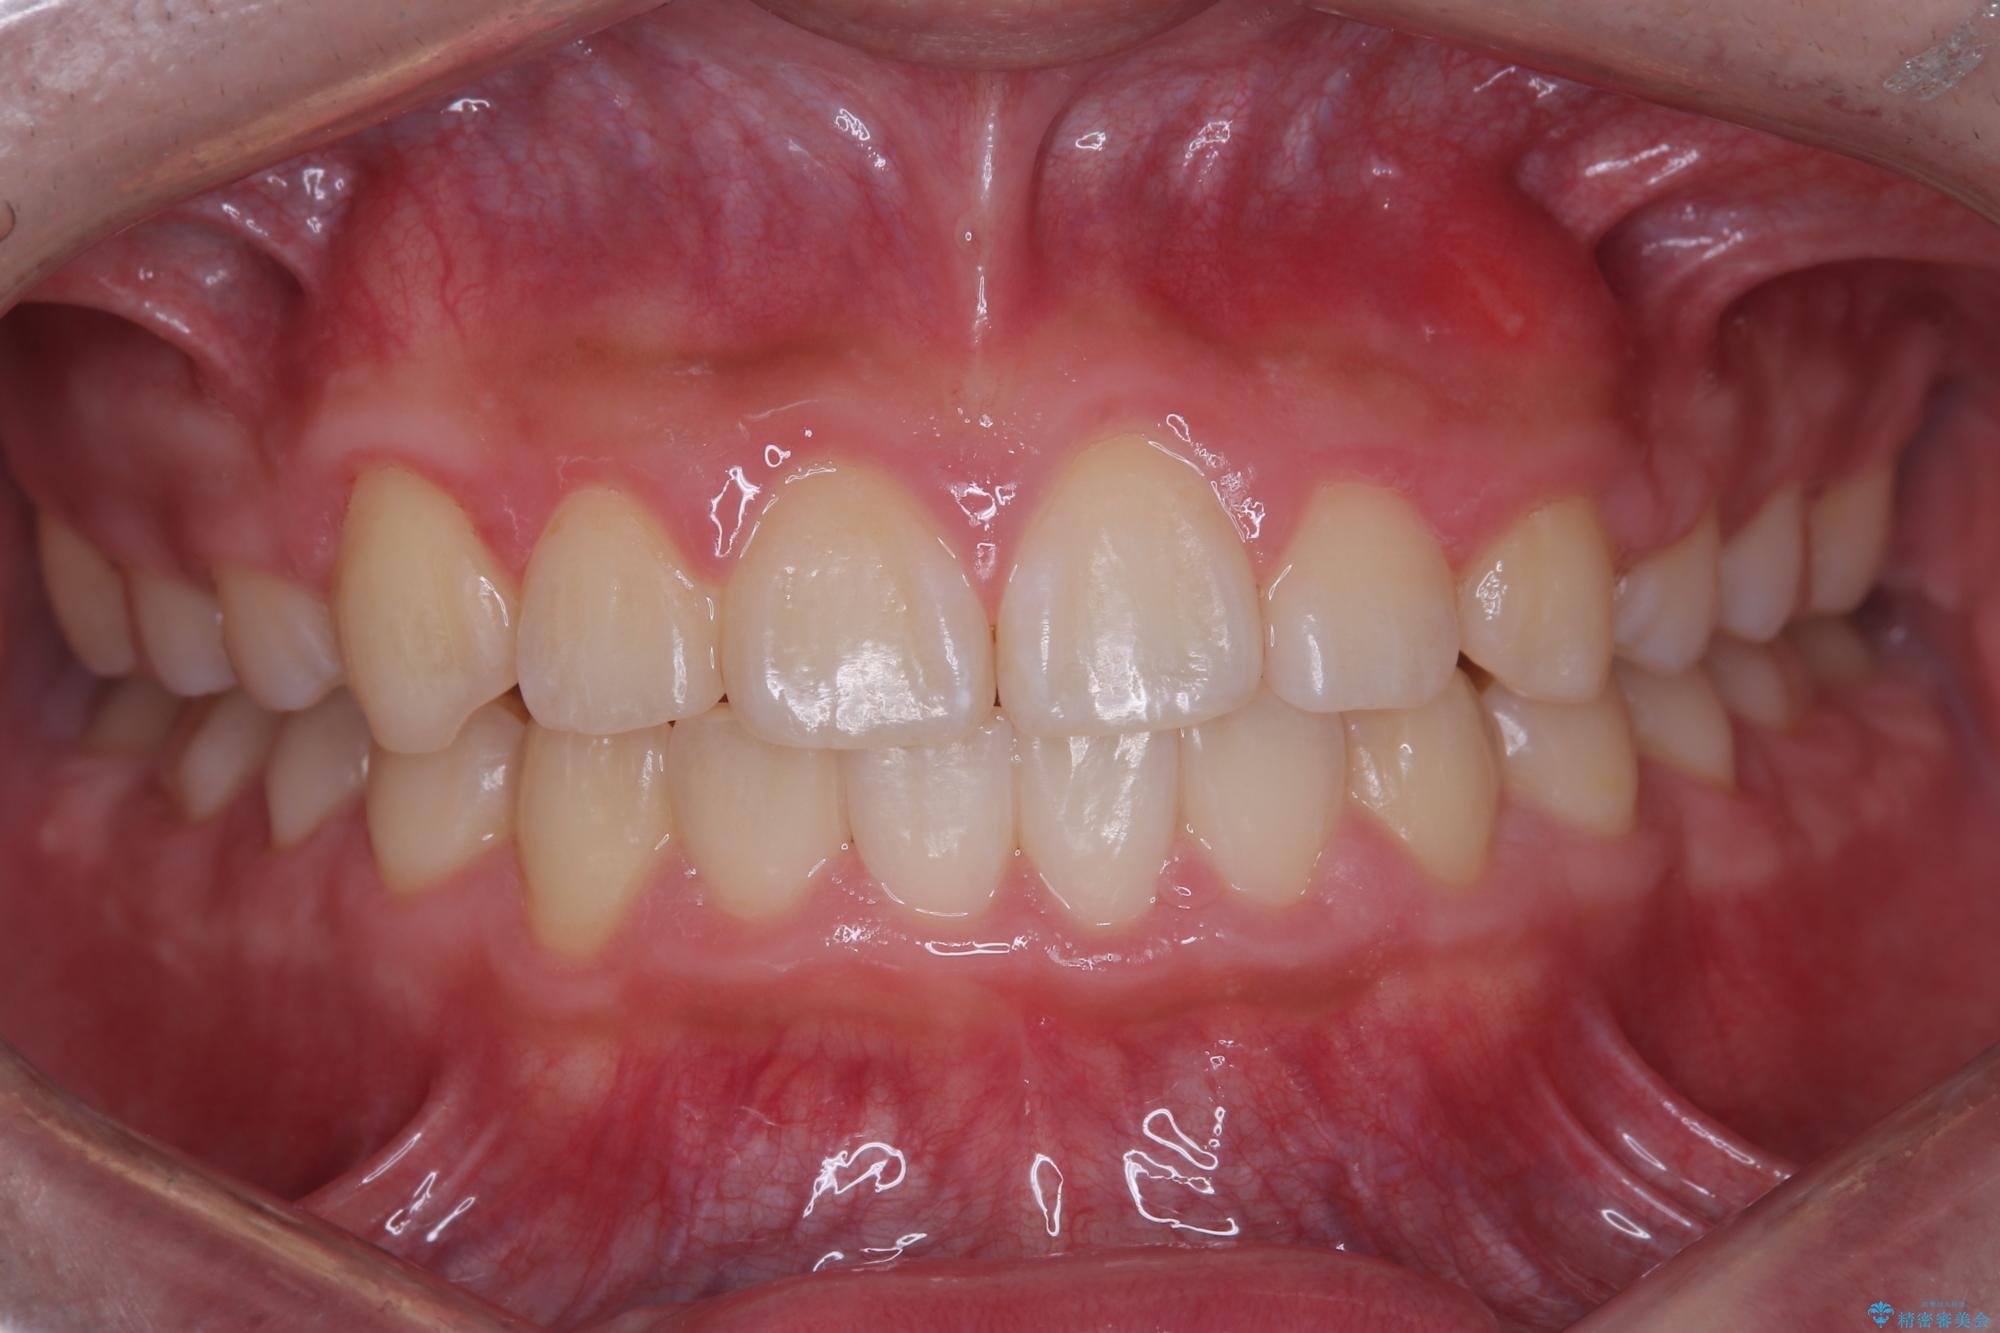

八重歯・歯並びのデコボコとディープバイトを改善した抜歯ワイヤー矯正症例

- 八重歯と咬み合わせを治したいを主訴にご来院された患者様です。

矯正の精密検査の結果上顎左右4番の計2本を抜歯し、審美性に配慮したワイヤー矯正装置(審美装置)を用いて治療を行いました。

八重歯などの歯列のデコボコが綺麗に改善され、患者様にも大変喜んでいただけました。また、咬み合わせが深い「ディープバイト」も併せて改善し、見た目だけでなく機能面でもバランスの取れた咬合を獲得しています。